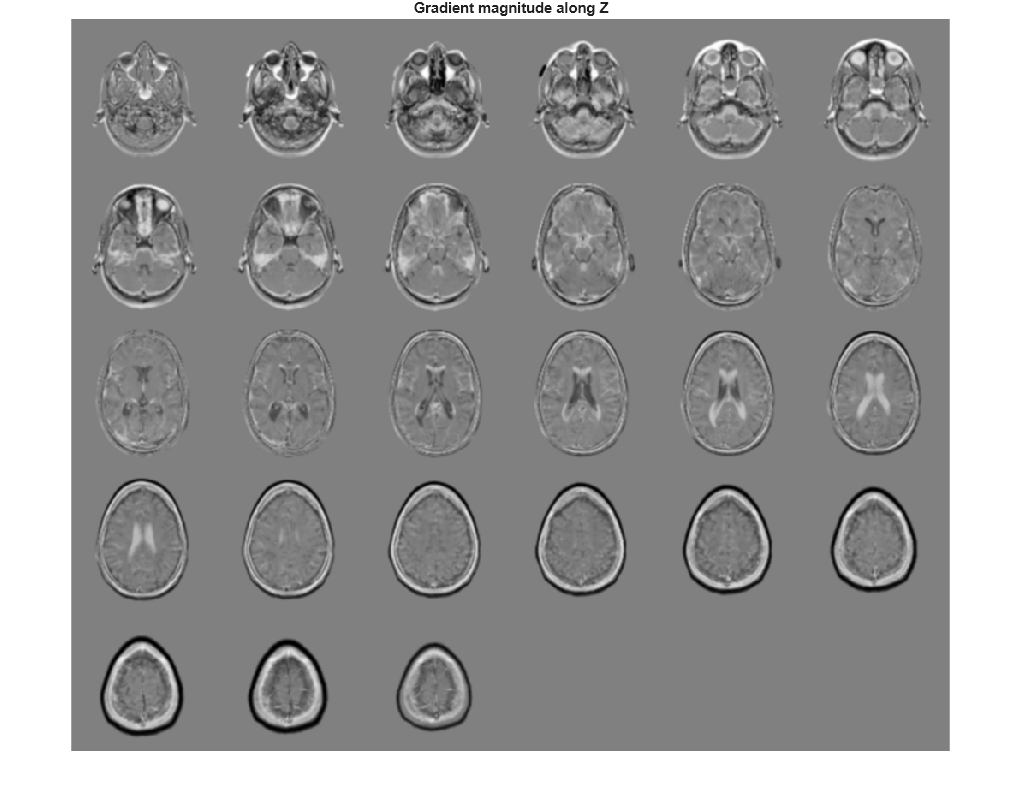

Visualize the directional gradients as a montage.

figure, montage(reshape(Gz,sz(1),sz(2),1,sz(3)),'DisplayRange',[]) title('Gradient magnitude along Z')

Depth gradient, returned as a 3-D numeric array of the

same size as image I. The depth

(z) axis points in the

direction of increasing plane subscripts.